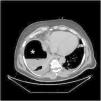

Varón de 49 años, sin antecedentes salvo por una tumorectomía renal derecha laparoscópica realizada hace un mes, por quiste Bosniak III-IV. Se presenta en urgencias con malestar general, dolor abdominal inespecífico y disnea. Se realiza inicialmente una radiografía de tórax (fig. 1), la cual es sugestiva de neumoperitoneo, seguida de un TAC abdominal (fig. 2) que muestra una colección subfrénica con nivel hidroaéreo. Durante la intervención quirúrgica se confirma una perforación de colon derecho retroperitoneal. Aunque las perforaciones de colon retroperitoneal suelen acompañarse de retroneumoperitoneo y abscesos retroperitoneales, en este caso no se identifican ninguna de las dos circunstancias, presentando únicamente un absceso subfrénico con nivel hidroaéreo, la cual, además, nos proporciona una falsa imagen de neumoperitoneo en la radiografía de tórax.